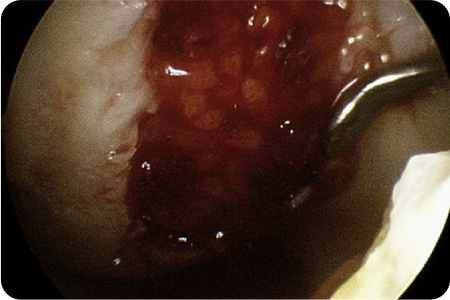

관절내시경을 통해 손상된 연골을 정리하고,

이식할 부위를 다듬습니다. 채취한 줄기세포를

특수 처리 후 손상된 관절 부위에 도포

하고

마무리합니다.